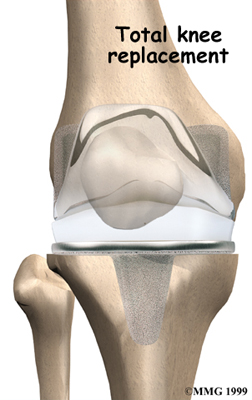

Artificial Knee Replacement

An artificial knee replacement is the ultimate solution for advanced knee OA.

Surgeons prefer not to put a new knee joint in patients younger than 60. This is because younger patients are generally more active and might put too much stress on the joint, causing it to loosen or even crack. A revision surgery to replace a damaged prosthesis is harder to do, has more possible complications, and is usually less successful than a first-time joint replacement surgery.

Related Document: FYZICAL Garland Campbell's Guide to Artificial Joint Replacement of the Knee